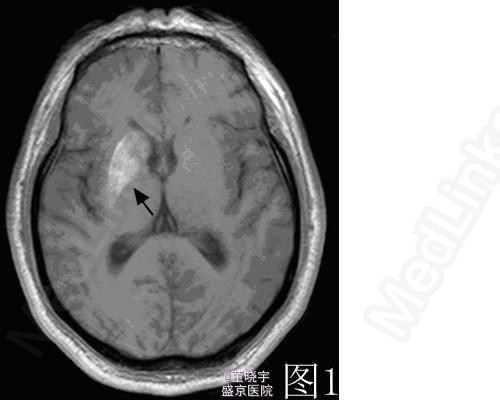

神经科查体:神志清楚,言语流利,双侧瞳孔等大,光反射灵敏,面纹对称,伸舌居中,四肢肌力5级,左侧肢体不自主运动,左侧肢体肌张力减低,深浅感觉及共济检查未见异常,双侧巴氏征-。 颅脑MRI检查:右侧基底节区T1WI高信号(图1)

诊断考虑:非酮症性高血糖合并舞蹈症 治疗上应用胰岛素控制血糖同时先后应用地西泮片、氯硝西泮等治疗效果均不明显,最后应用氟哌啶醇1mg日二次口服治疗,3日后患者症状好转后出院